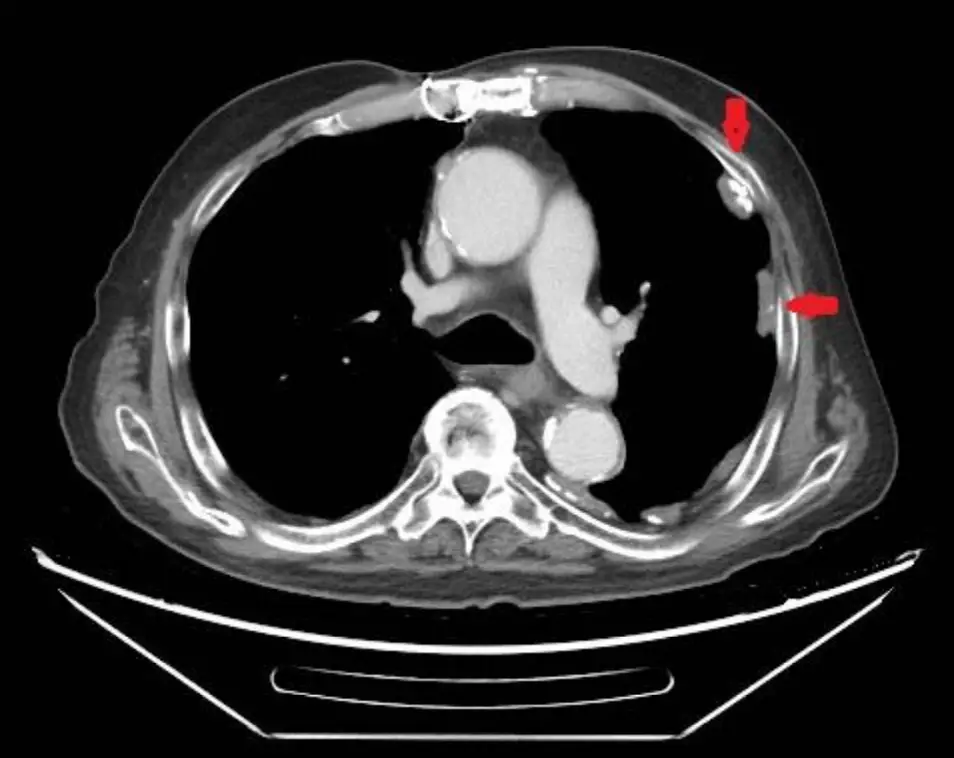

72歲海軍退休輪機士官長,長年在軍艦輪機房工作。最近因為喘,在門診就診,胸部X光異常,於是接受 胸部電腦斷層檢查如附圖,下列何者敘述為是? (1) 電腦斷層顯示為胸膜斑(pleural plaques) (2) 與工作環境息息相關 (3) 不會引起肺癌 (4) 與胸腔間皮瘤高度相關 (5) 抽煙對於癌症的發生率不會有加成效果

電腦斷層橫切面可見左右肋胸壁內側呈桌狀、沿壁層胸膜分布之高密度局灶鈣化,亦沿葉間裂與橫膈頂端見類似鈣化板狀陰影;肺實質並未見結節或間質性纖維化。典型「桌板狀」(table-like)鈣化、位於壁層胸膜而非肺葉間,是石棉相關胸膜斑的經典影像特徵,支持良性石棉性胸膜病變的診斷。